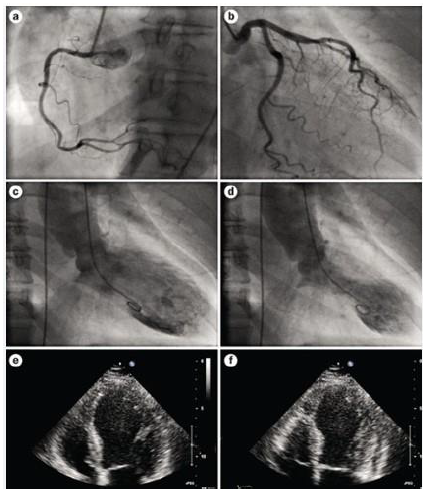

Paciente, 72 anos, hipertensa, não diabética, não tabagista, foi trazida pelo SAMU à sala de emergência com quadro de precordialgia típica súbita, palpitações e sudorese difusa, após receber um telefonema com um suposto sequestro de seu filho. Após a avaliação inicial, foram realizados ECG, ECO, troponina (resultado três vezes o valor de referência) e cineangiocoronariografia.

Fonte: https://www.nature.com/articles/nrcardio.2010.16 consulta em 25/02/2024.

V. Síndrome de Takotsubo.